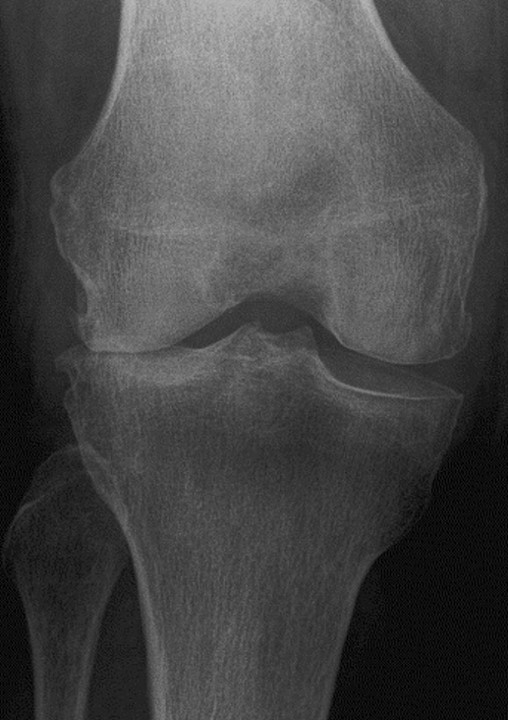

骨關節炎是最常見的關節炎,全球有數百萬的人們患有此病。隨著時間推移,骨骼末端起緩衝作用的保護性軟骨不斷磨損,就會發生該疾病。

雖然骨關節炎可能損害任何關節,但疾病最常影響膝蓋、髖關節和脊柱中的關節。

雖然關節損傷是不可逆的,但骨關節炎的症狀通常可進行控制。保持活動狀態、維持健康體重和接受幹細胞治療可減緩疾病進展,並有助於改善疼痛和關節功能。